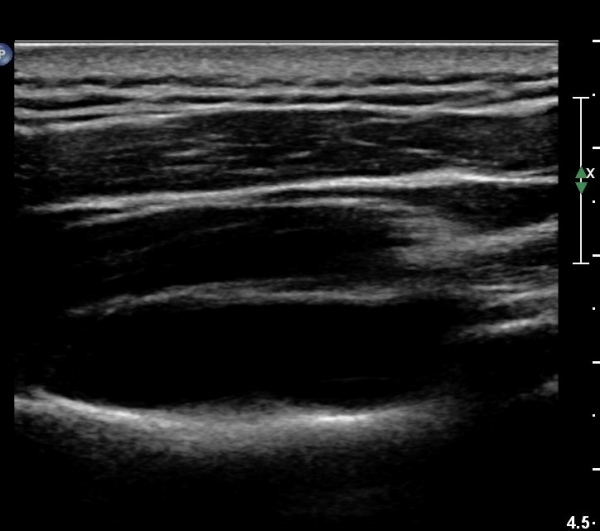

ÃÊÀ½ÆÄÀ¯µµÇÏ ÈíÀÎÄ¡·á Áß ÁÖ»ç¹Ù´ÃÀÌ ¼ö¾×³»¿¡ Á¤È®È÷ À§Ä¡ ÇÑ °ÍÀÌ °üÂûµÈ´Ù(»çÁø 7).

ÃÊÀ½ÆÄÀ¯µµÇÏ ÈíÀÎÄ¡·á ÈÄ ´ëºÎºÐÀÇ ¼ö¾×ÀÌ Á¦°Å µÈ °ÍÀÌ È®ÀεȴÙ(»çÁø 8).